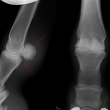

První karpální kůstka - kost, která se vyskytuje u malého % koní

Fragment na spěnkové kosti